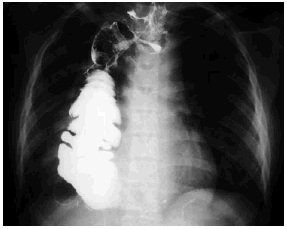

La TC torácica evidenció una importante dilatación esofágica con nivel hidroaéreo, acompañándose de gran tumoración de densidad de partes blandas en el mediastino posterior (fig. 3), correspondiente a la pared esofágica muy engrosada.

Fig. 3.